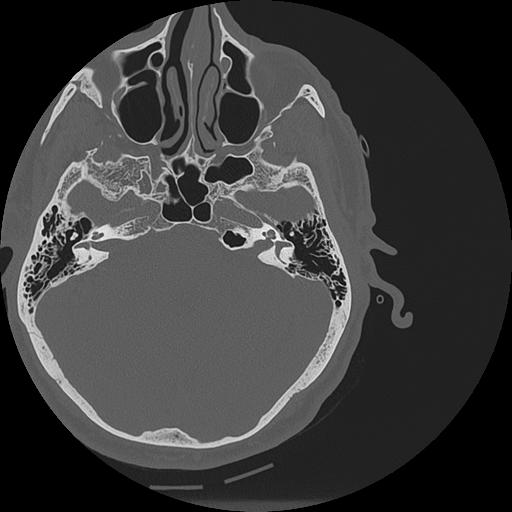

7 HUESO,,Vol,0.5,HUESO,,